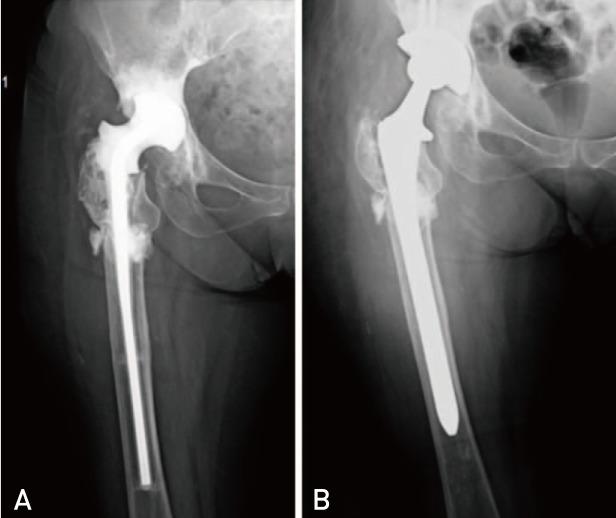

Periprosthetic joint infection (PJI) due to is rare. It frequently occurs patients receiving immunosuppressive medicine. We describe two periprosthetic infection of two immunocompromised patients. Both of patients were receiving azathioprine and prednisolone therapy. First patient presented six years after total hip arthroplasty with a huge abscess on her right thigh that was reached to femoral component through the lytic area of lateral femur. Second patient presented with drainage from his hip and he had undergone two-step revision surgery for PJI 3 months ago. There is no consensus in the treatment of periprosthetic salmonella infections. We prefer two-step revision surgery for these infections as previously described in the literature.